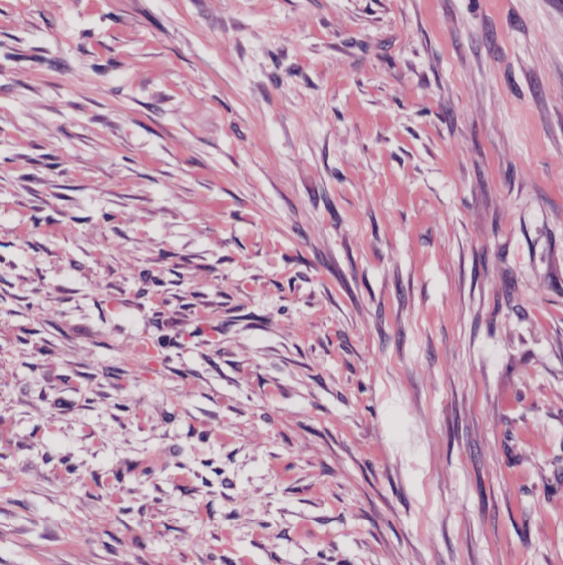

Ulcerated mass in the colon. ▶️Geographic necrosis ▶️Lots of mitoses & apoptotic bodies ▶️Sheet-like & trabecular growth ▶️Highly atypical nuclei w/ prominent nucleoli ▶️Eosinophilic cytoplasm Based on 🔬H&E morphology, what is your diagnosis? #PathTwitter #GIPath

Miruna Popescu, MD tweet mediaMiruna Popescu, MD tweet mediaMiruna Popescu, MD tweet mediaMiruna Popescu, MD tweet media